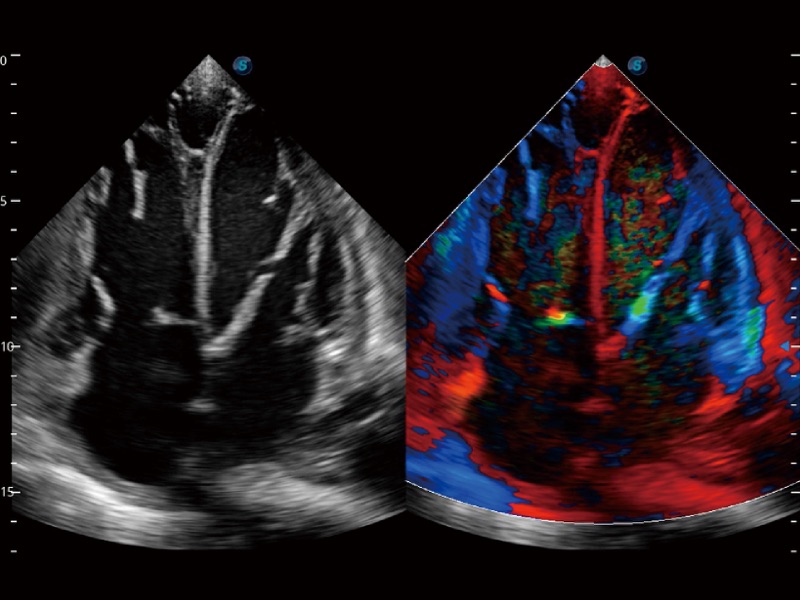

心血管应用

支持运动和药物负荷协议、多心动周期存储选择,为临床观察心肌负荷状态下的室壁节段运动、评估心肌缺血状态提供更多的解决方案。

通过心肌识别技术和二维斑点追踪技术相结合,计算心肌各节段的应变应变率、速度、位移并以曲线图显示,实现整体或者局部心肌定量分析。同时可呈现牛眼图直观和准确诊断心肌的运动情况。

血管内中膜的厚度值是预测心血管疾病风险的重要指标,Auto IMT可以实现血管近场和远场内中膜厚度的自动测量,为临床提供快捷有效的诊断工具。